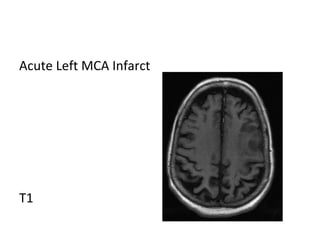

Acute Left MCA Infarct

T1

b) Acute Infarct (6-72 hours) :

-The acute infarct is characterized by increase in

vasogenic edema and mass effect

-Damaged vascular endothelial cells cause leakage of

extracellular fluid and increase the risk of

hemorrhage

-On imaging , there is increased sulcal effacement and

mass effect , the mass effect peaks at 3-4 days which

is an overlap between the acute & early subacute

phases

-MRI shows hyperintensity of the infarct core on T2 ,

best seen on FLAIR , the FLAIR abnormality is usually

confined to the grey matter , DWI continues to show

restricted diffusion

-There may be some arterial enhancement due to

increased collateral flow

-Perfusion images most commonly show increase in

size of the infarct core with resultant decrease in size

of penumbra